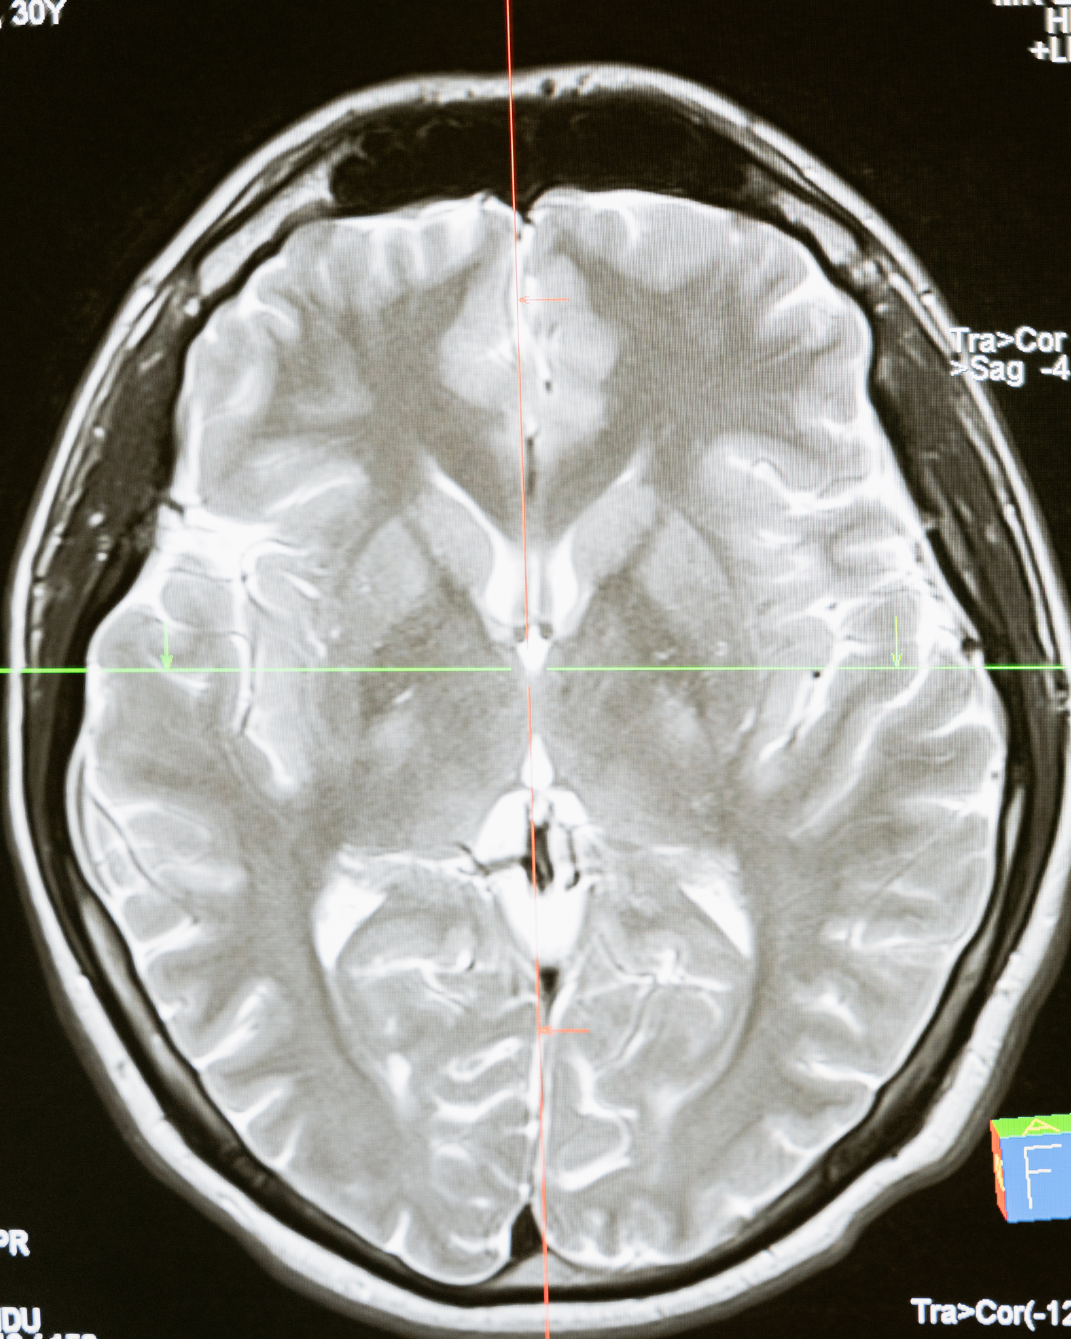

A traumatic brain injury can affect far more than a person’s immediate physical health. Brain injuries can interfere with memory, concentration, mood, speech, balance, sleep, and the ability to work or carry out daily activities. In severe cases, the effects may be permanent.

Brain injuries often result from car accidents, truck accidents, motorcycle accidents, bicycle accidents, pedestrian accidents, slip and falls, and other serious incidents. Even a concussion or mild traumatic brain injury should be taken seriously, especially when symptoms do not resolve quickly.